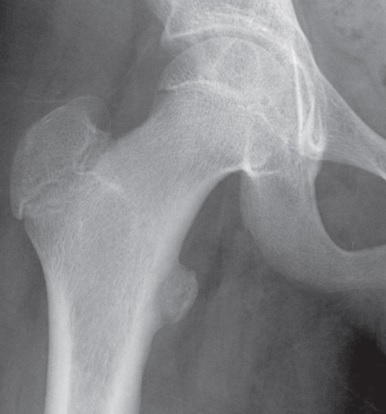

4

Q

Qual o diagnóstico?

A

Lesão epifisária excêntrica

Fise aberta

Dx: condroblastoma